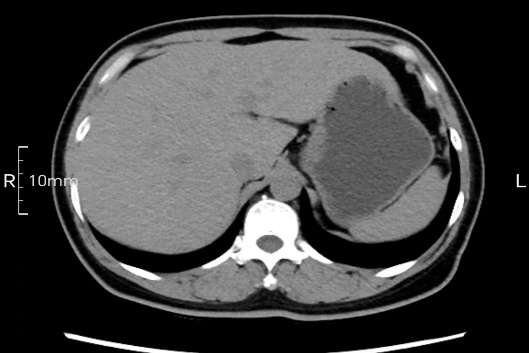

看看下面三幅便知遵醫(yī)囑的重要性。

完美禁食且喝飽飽,胃壁完美展現(xiàn)。

CT檢查前的“禁食”和“喝飽”,看似矛盾,實(shí)則合情合理,分工合作:空腹:是為了讓上腹部(肝膽胰脾腎等)的圖像清晰無干擾,并保障檢查安全。喝水:有效的充盈胃部和、腸道使圖像清晰呈現(xiàn)。兩者巧妙配合,都是為了給您一個(gè)最精準(zhǔn)的診斷結(jié)果。